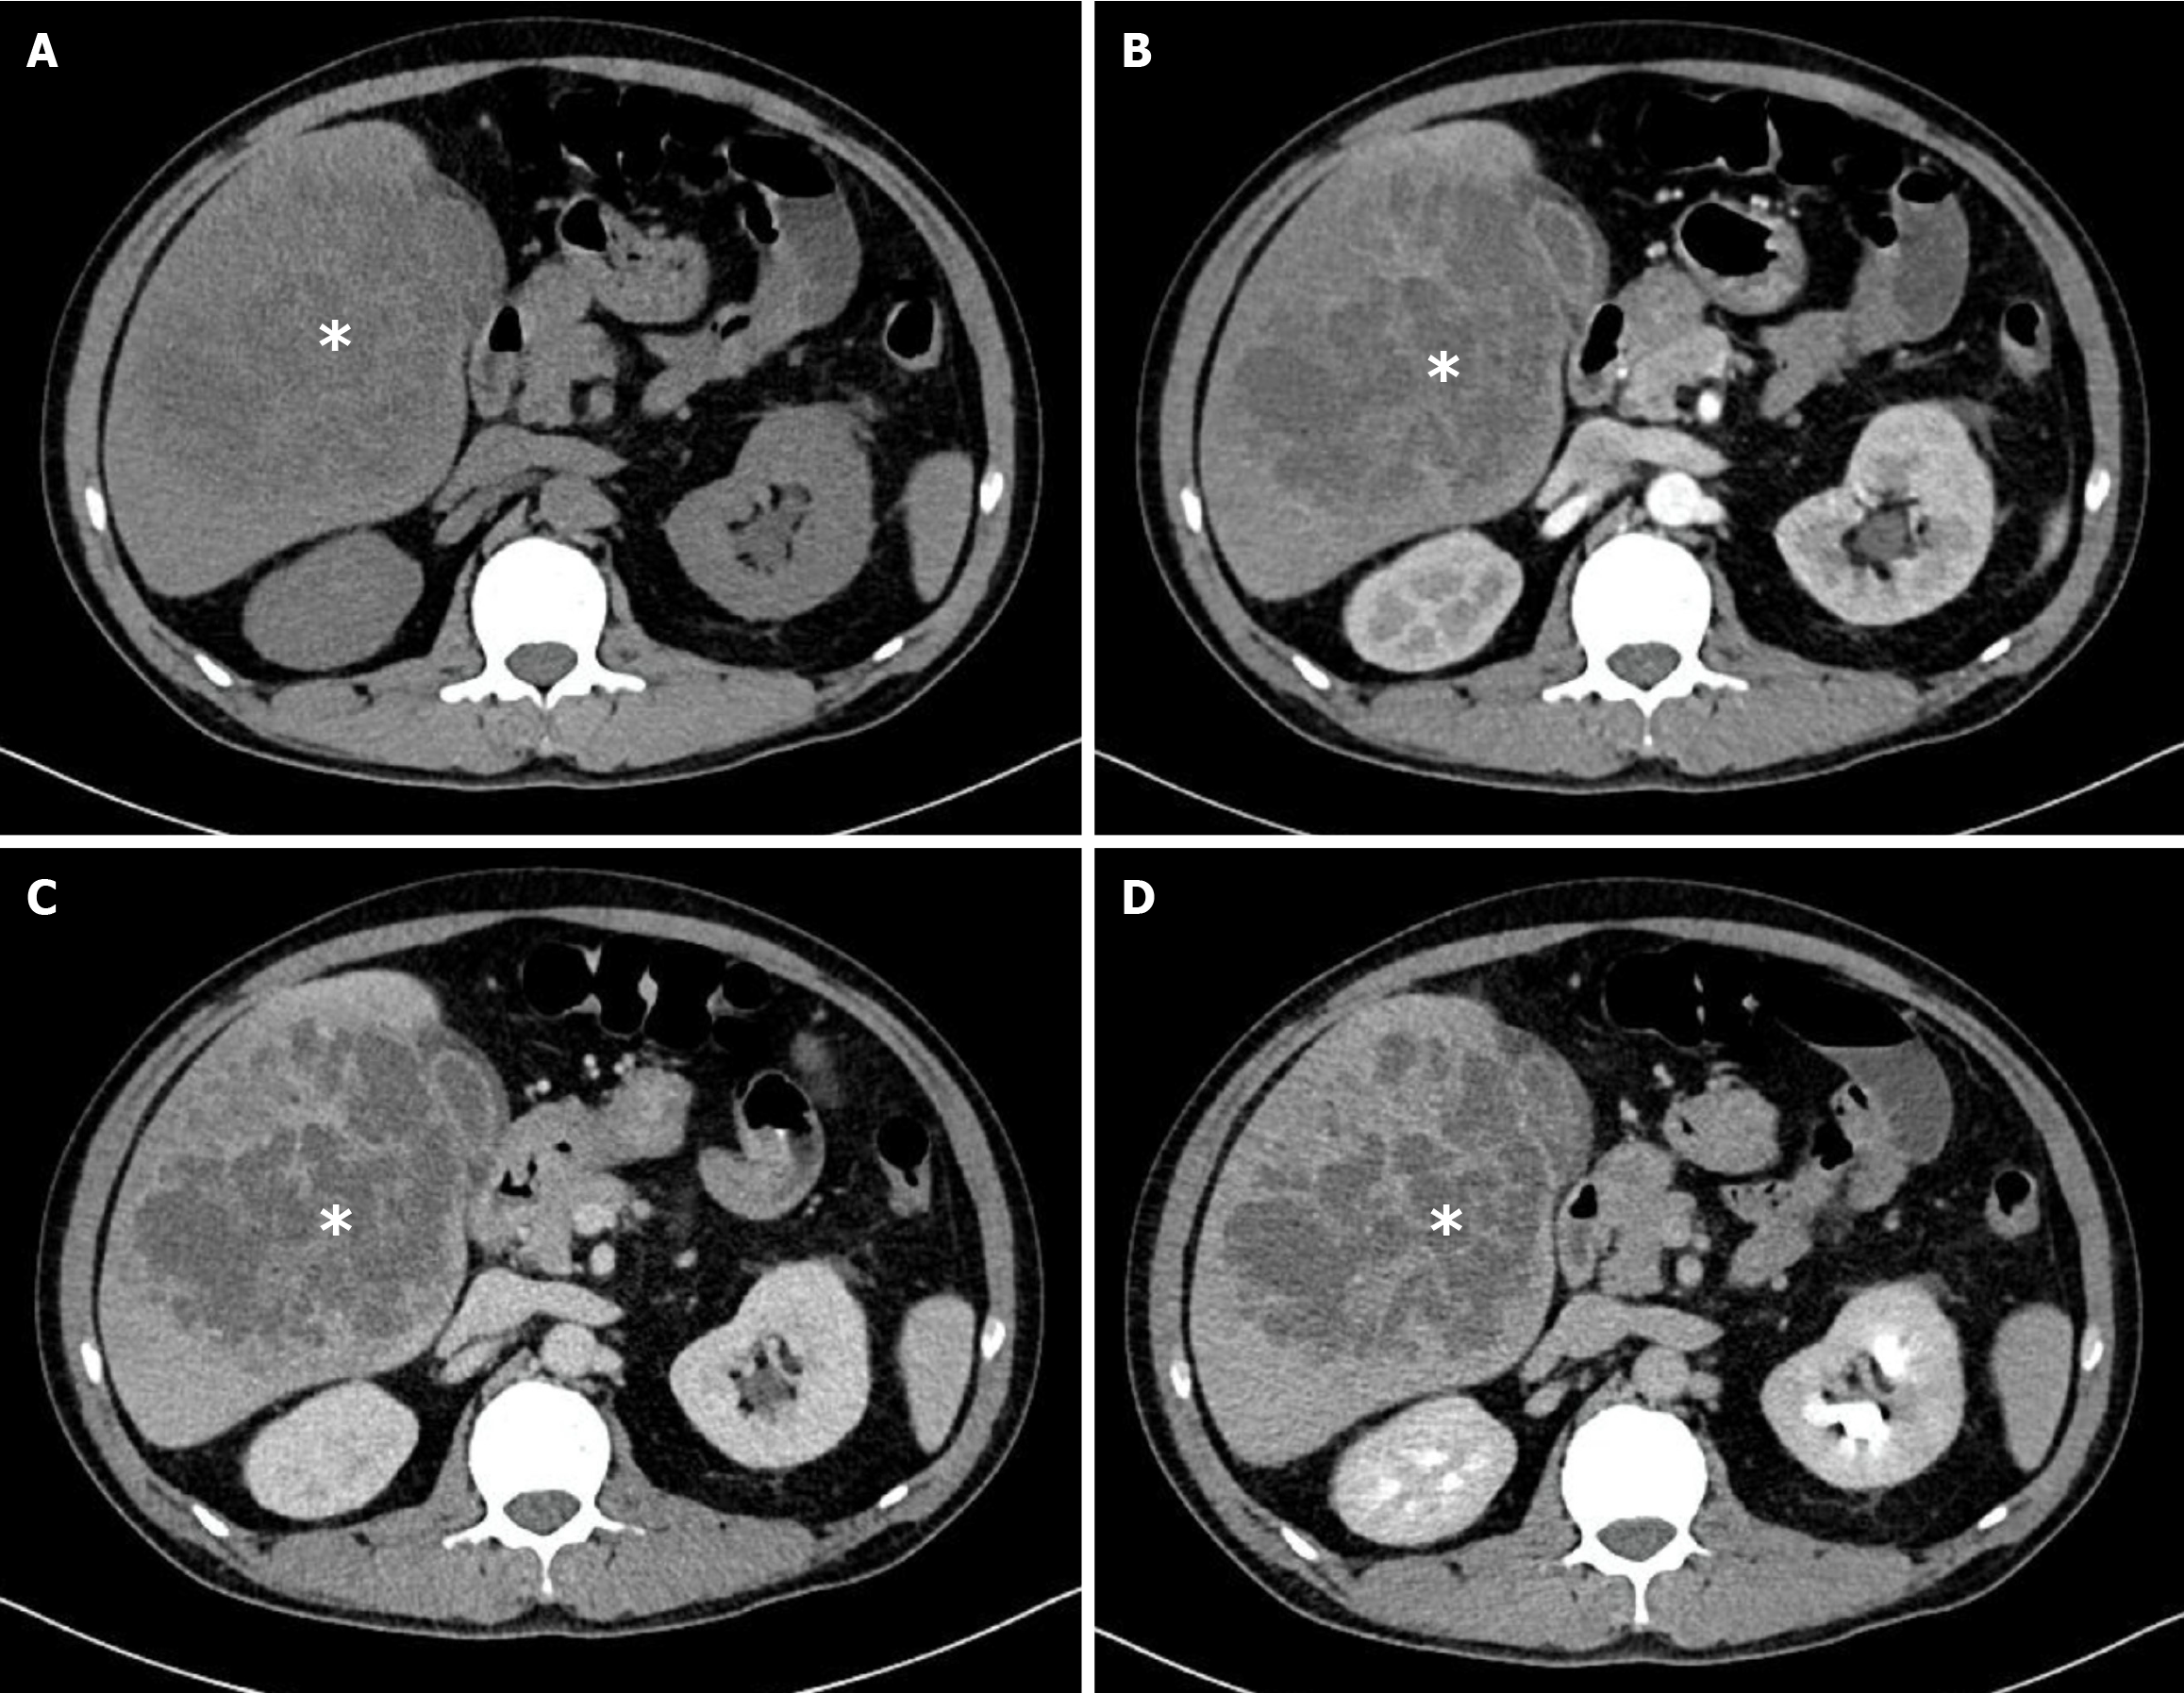

Figure 4 Multiphase computed tomography images of a pyogenic liver abscess caused by Streptococcus species (white asterisks).

The cavity shows slightly irregular margins but homogeneous, non-septated internal architecture with rim enhancement. This contrasts with most Klebsiella pneumoniae liver abscesses, which typically demonstrate heterogeneous internal architecture. A: Non-contrast phase; B: Arterial phase; C: Portal venous phase; D: Delayed phase.